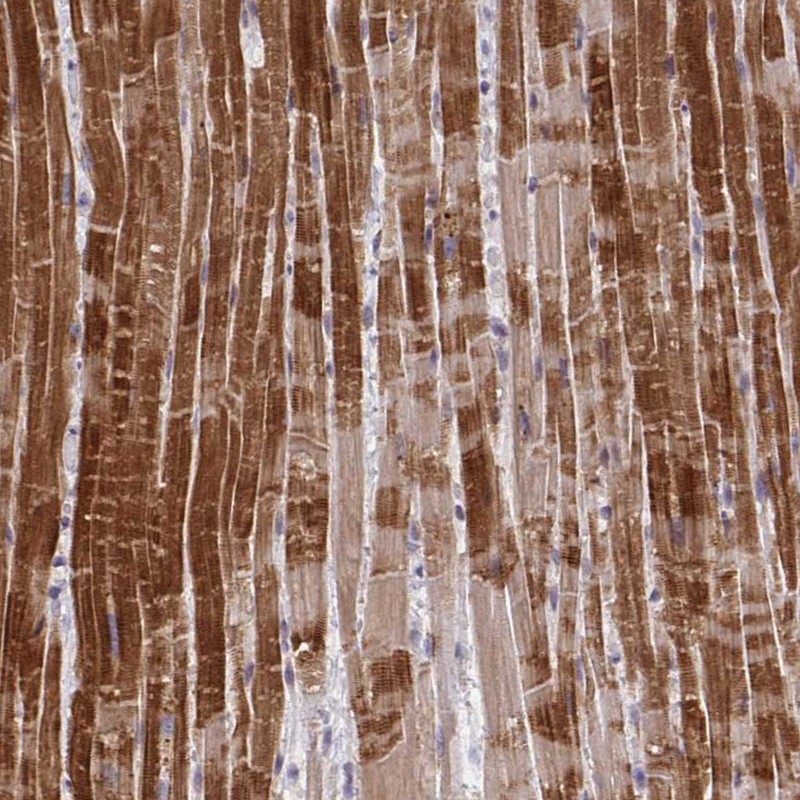

Immunohistochemical staining of human heart muscle shows strong cytoplasmic positivity in myocytes.